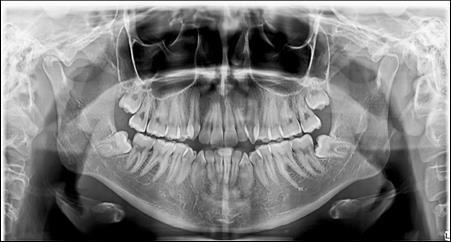

The panoramic radiograph showed bilateral mandibular third molars. The level of alveolar bone crest was within the normal range. (Figure 3)

Figure 3.Pretreatment panoramic X-ray

Pretreatment panoramic X-ray